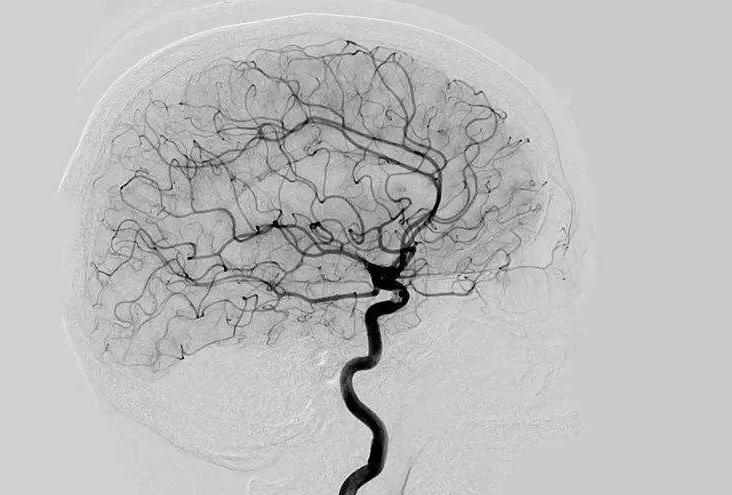

Digital Subtraction Angiography 血管造影机应注意什么?

Digital Subtraction Angiography 血管造影机又称数字减影血管造影机,是通过电子计算机进行辅助成像的血管造影方法,应用计算机程序进行两次成像完成的。在注人造影剂之前,第一次成像工作,图像转成数字信号储存,注人造影剂后,再次成像并转换成数字信号,两次数字相减,消除相同的信号,得到只有造影剂的血管图像。临床主要应用于冠心病、心律失常、瓣膜病和先天性心脏病的诊断和治疗。